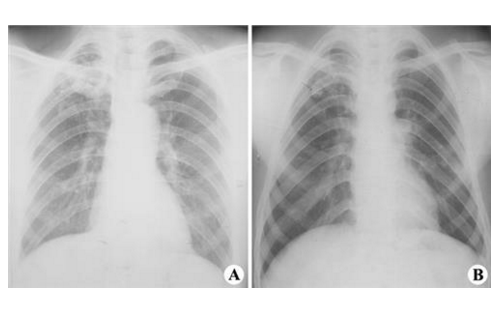

肺結核圖片

空洞型肺結核能活多久 (7)

空洞型肺結核能活多久 (8)

空洞型肺結核能活多久 (9)